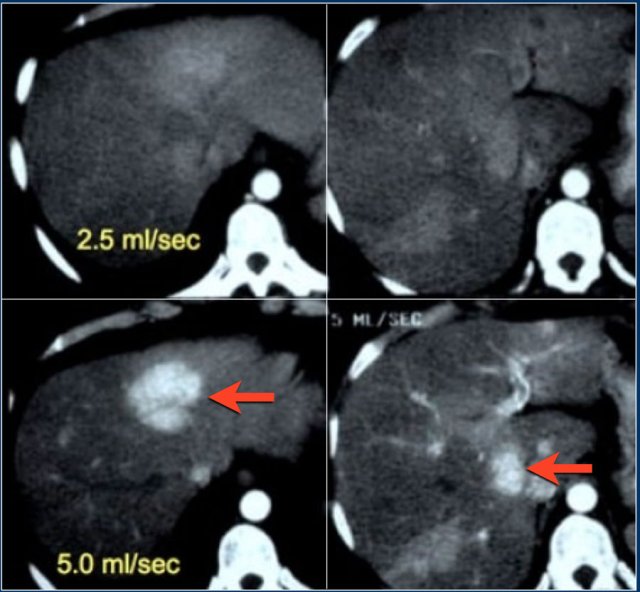

The upper images are of a patient with liver cirrhosis and multifocal hepatocellular carcinoma examined after contrast injection at 2.5ml/sec.

Because of poor enhancement the examination was repeated at 5ml/sec.

There is far better contrast enhancement and better tumor detection.